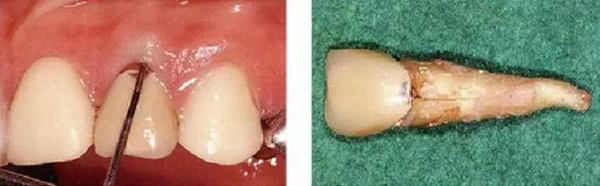

●外傷引起的附著喪失②

右上2修復物脫落而來院的患者(上圖是修復物臨時裝戴的照片)。頰側僅有一點有6mm的牙周袋。5個月前不存在此牙周袋。診斷為無法保存而進行了拔牙。拔牙后,肉眼可清晰觀察到破折線。根據(jù)診查推斷為該深度牙周袋是由于牙根破折導致附著喪失,細菌沿著破折線進入后破壞了牙周膜造成的。